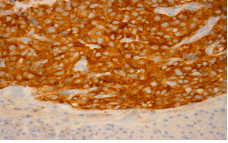

Figure 5c Low antibody staining against Ki-67 (nuclear protein present during all active phases of cell cycle and absent from resting cells).

Figure 5d Intense staining against synaptophysin (citoplasmatic protein located in neurons and neuroendocrine tumors).